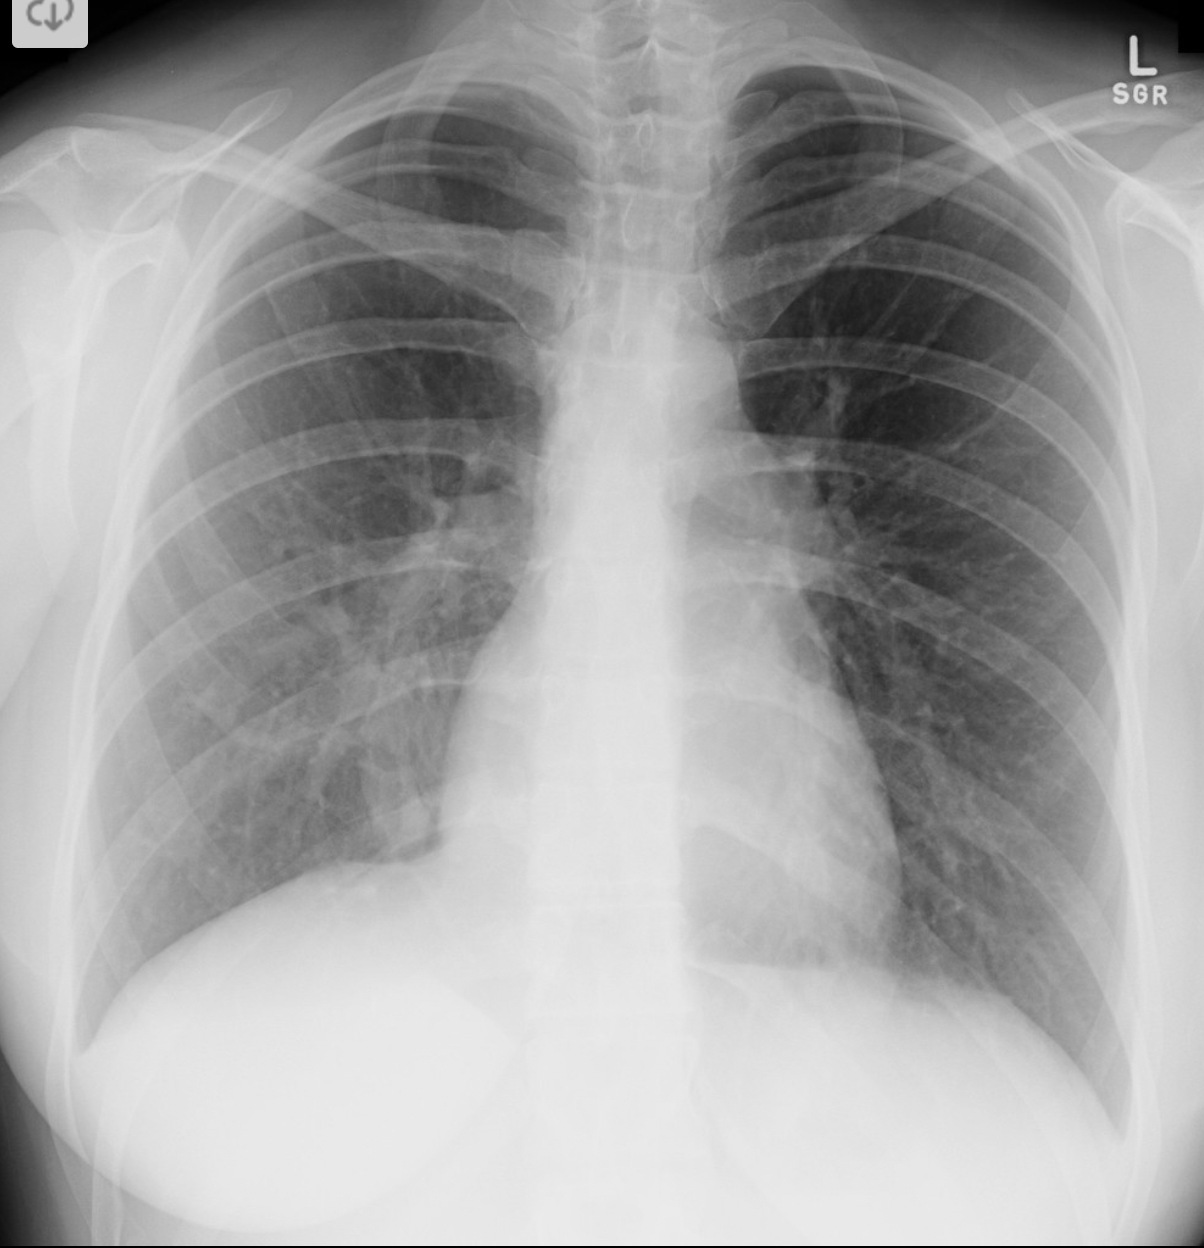

2

A

Scimitar syndrome (Anomalous right lower pulmonary vein draining into IVC)